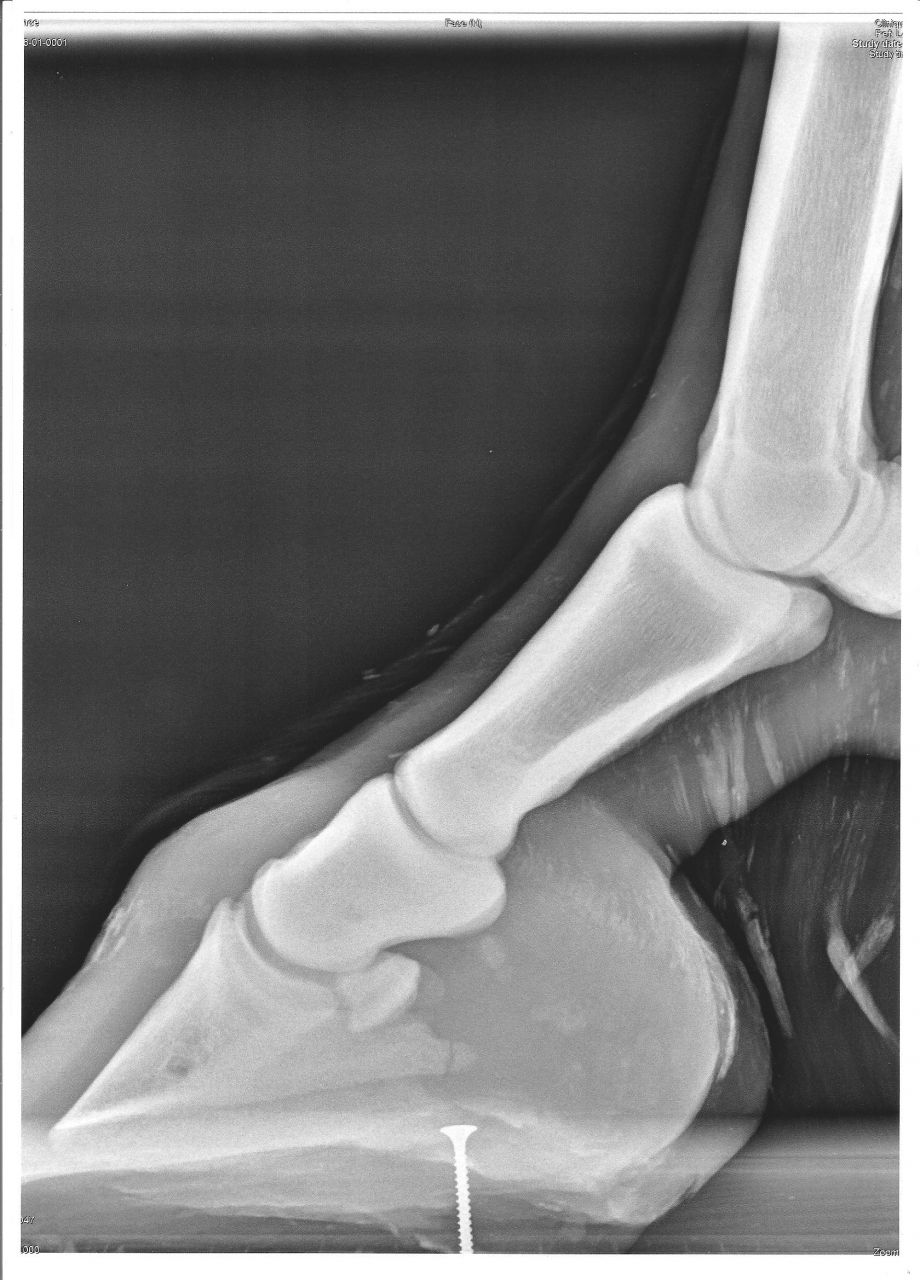

| Dire merci | Mon loulou a eue une fracture du processus palmaire ( os du talon ) qui, d'après mon véto et MF ne se ressoudera pas... Ce n'est pas douloureux et ne fait pas boiter. les conséquences et séquelles à long terme de cette fracture ne sont pas connue car on ne s'en apperçoit pas si on ne fait pas une radio du pied... donc, certains chevaux ont çà, sont montés et vivent normalement, sans que leur proprios le sachent... Mais j'aimerai trouver des articles et/ou témoignages sur tous çà... Quelqu'un saurai ou je pourrais trouver ces infos ? Merci d'avance |

| Dire merci | les radios: La fracture est juste au dessus du vis ( qui n'est pas dans le sabot ) |